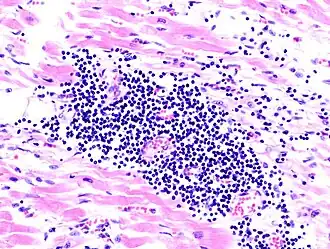

Myocarditis is een ontsteking van het myocard (het hartspierweefsel).